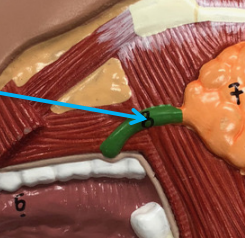

Parotid Duct

The duct that carries saliva from the parotid gland into the oral cavity. It typically opens into the vestibule of the mouth (the space between the cheek and gums) near the upper second molar tooth.